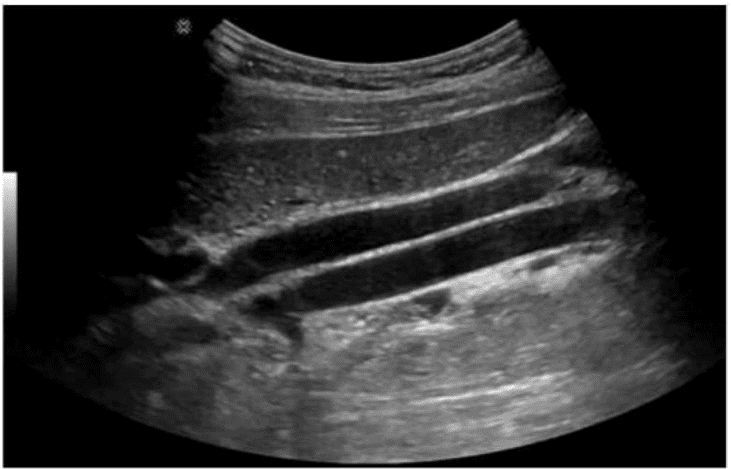

Which scanning approach was utilized to obtain this image?